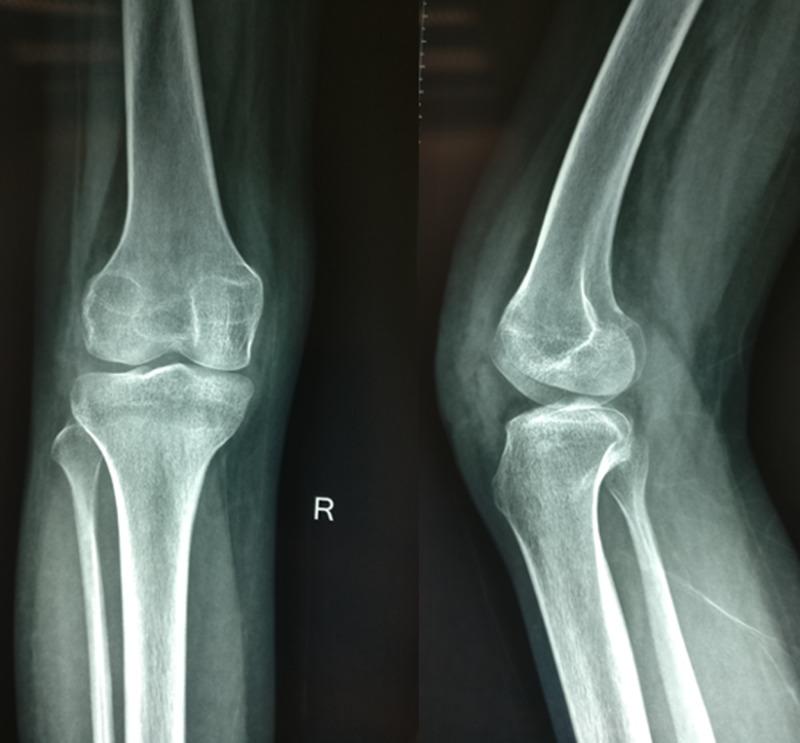

A 15-year-old girl presented with pain and swelling on the anterior aspect of the right knee for one year. The radiological evaluation with x-rays and magnetic resonance imaging suggested a benign aggressive lesion of the right patella with a cortical breach. Core needle biopsy of the lesion revealed it to be a giant cell tumor (GCT). She was treated with total patellectomy and end-to-end repair of quadriceps to the patellar tendon. The histopathological report of the whole specimen revealed it to be a GCT with secondary aneurysmal bone cyst (ABC). After 24 months, she was asymptomatic, and there was no evidence of local recurrence or distal metastasis. An extensive review of the literature revealed only four cases of combined GCT with secondary ABC in the patella. Though rare, GCT with secondary ABC of the patella should be kept as a differential diagnosis for anterior knee pain and swelling in young patients. The diagnosis is solely based on histopathological findings. It is imperative to obtain a precise tissue diagnosis in the preoperative period to plan appropriate treatment.

一名15岁女孩因右膝前部疼痛和肿胀就诊,症状已持续一年。X线和磁共振成像的影像学评估显示右髌骨有一个良性侵袭性病变,伴有皮质破坏。对该病变进行的粗针穿刺活检显示为骨巨细胞瘤(GCT)。她接受了全髌骨切除术,并将股四头肌与髌腱进行端端修复。整个标本的组织病理学报告显示为伴有继发性动脉瘤样骨囊肿(ABC)的骨巨细胞瘤。24个月后,她没有症状,也没有局部复发或远处转移的迹象。广泛的文献回顾显示,仅有4例髌骨合并继发性ABC的骨巨细胞瘤病例。虽然罕见,但髌骨继发性ABC的骨巨细胞瘤应作为年轻患者膝前疼痛和肿胀的鉴别诊断之一。诊断完全基于组织病理学检查结果。术前获得精确的组织诊断以规划适当的治疗至关重要。